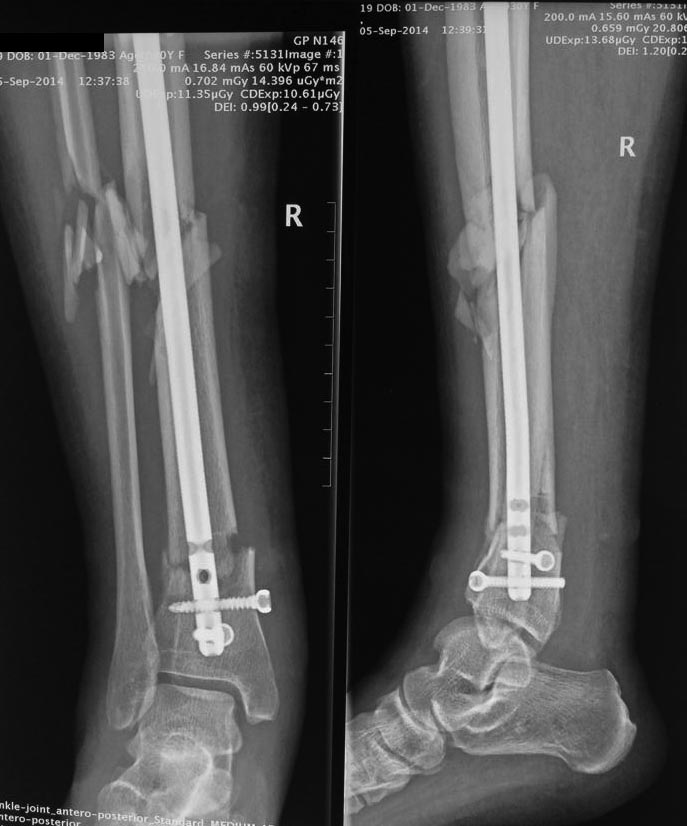

Что посоветуете, друзья. Оперировалась 2,5 мес назад, в одной из московских клиник, при ранней активизации через 1,5 мес появилась такая деформация, плюс имеются в области нижней трети голени свищи с незначительным отделяемым

Здравствуйте, коллеги! Насколько я понимаю, у пациента инфицированный перелом! На снимках видно остеолизис вокруг дистальных замыкающих шурупов! На мой взгляд, небходимо удалить гвоздь, произвести некректомию и наложить аппарат Илизарова. Интересно посмотреть первичные снимки! С Уважением!